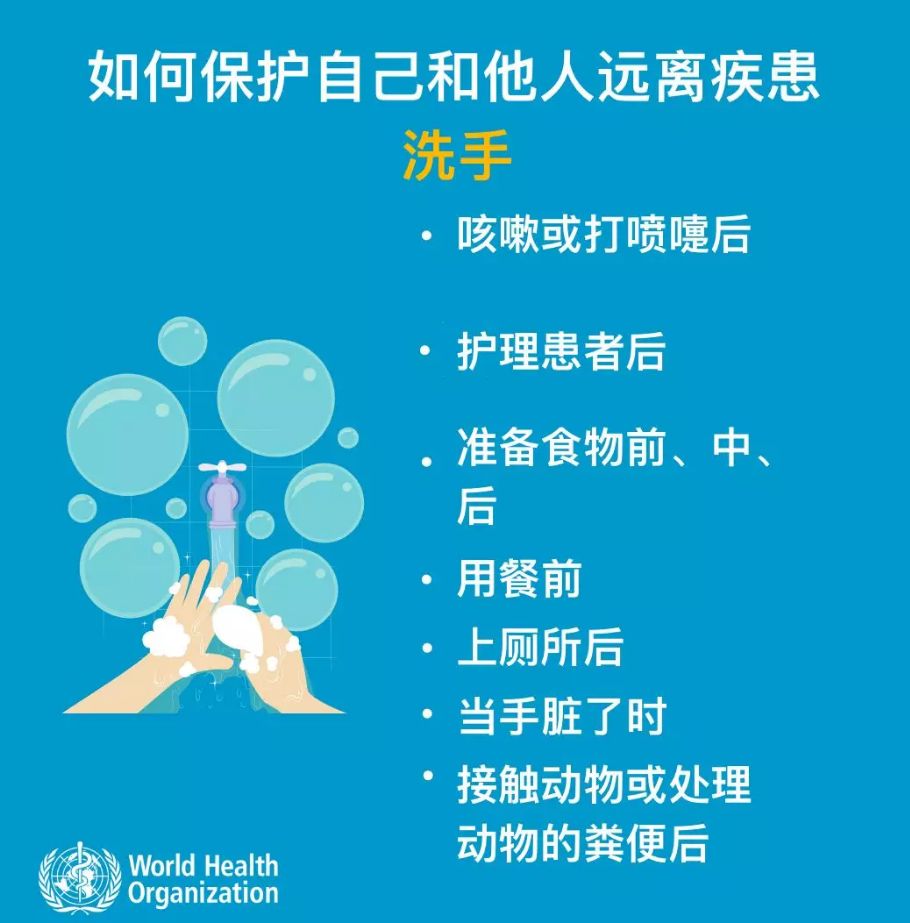

注意卫生

定期洗手,特别是在与病人直接接触后;有急性呼吸道感染症状(如咳嗽和打喷嚏)时用干净纸巾遮盖口鼻并擦拭干净,过后洗手;并且与病人保持适当距离。

(图片来源于网络)